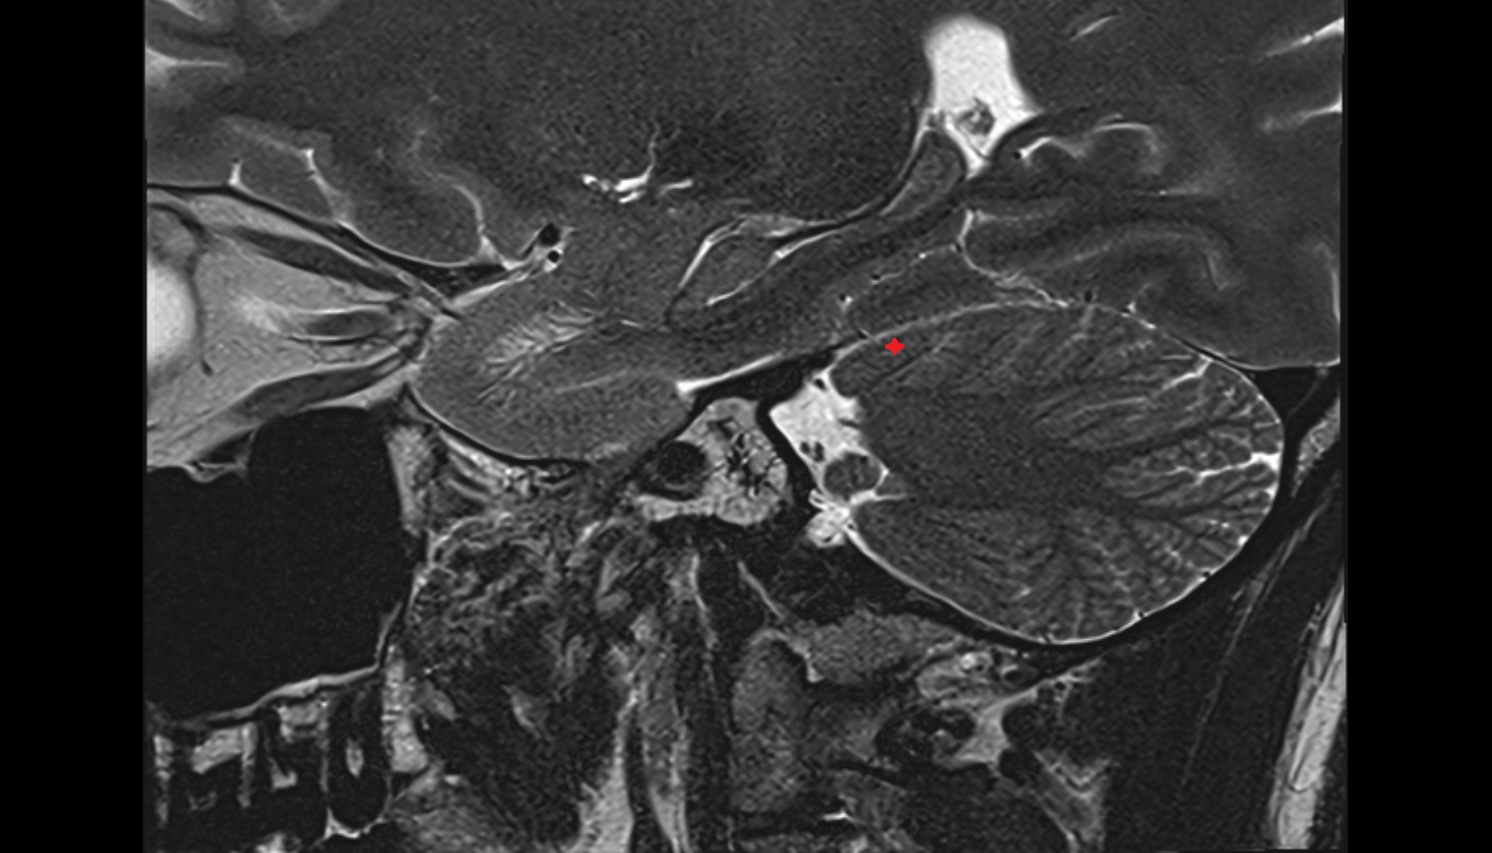

- Cerebellum

- Flocculus

- Crus I of ansiform lobule of cerebellum

- Crus II of ansiform lobule of cerebellum

- Paramedian lobule (HVII) of cerebellum

- Simple lobule (HVI) of cerebellum

- Anterior quadrangular lobule (HV) of cerebellum

- Anterior quadrangular lobule (HlV) of cerebellum

- Biventral lobule (HVIII) of cerebellum

- Cerebellar tonsil (H IX)